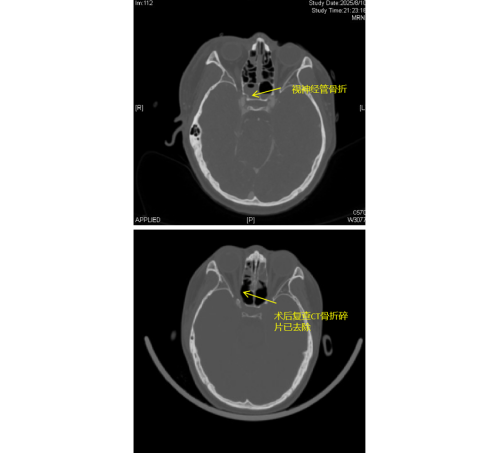

急诊科。经检查发现,李琦存在颅底多处骨折、面颅多发骨折,尤其危急的是右侧视神经管骨折,碎裂的骨片直接压迫视神经及邻近的颈内动脉,导致右眼瞳孔散大、对光反射消失,视力完全丧失,病情极为危重。

由于视神经管周围解剖结构复杂,上方毗邻前颅底,下方紧邻颈内动脉和海绵窦,稍有不慎就可能导致脑脊液鼻漏、视神经断裂甚至颈内动脉破裂出血等严重后果,因此视神经的特殊位置被视为“手术雷区”。加之操作空间小,手术难度大,对于医生而言是一个巨大的挑战。视神经与鼻窦相邻,用鼻内镜经鼻窦进行视神经管减压手术,视野清楚、损伤最小。在手术过程中,康晓明医生利用高清鼻内镜,精准地清除了压迫视神经的骨折碎片,有效降低了神经压力。

手术完成后即刻观察到李琦右眼对光反射恢复灵敏,经过系统的治疗,其右眼视力已恢复至0.1,术后效果显著。目前,李琦正在进一步康复治疗中。此类高难度手术的成功,不仅展现了立博体育